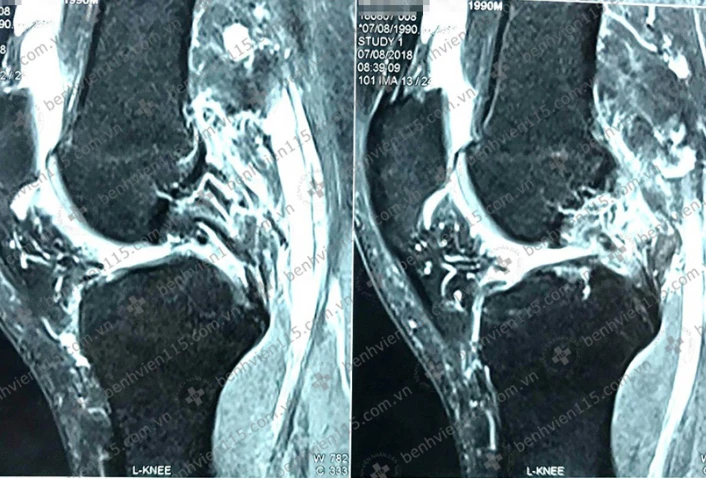

Kết quả chụp MRI cho thấy anh K. bị đứt dây chằng chéo trước và dây chằng chéo sau. Ảnh: BV cung cấp

Qua thăm khám và chẩn đoán hình ảnh, các bác sĩ (BS) khoa Y học thể thao BV Nhân dân 115 ghi nhận anh K. sưng đau, lỏng gối trái, bị đứt dây chằng chéo trước, dây chằng chéo sau. Ngoài ra còn bị rách sụn chêm gối trái nên các BS quyết định phẫu thuật cho bệnh nhân.